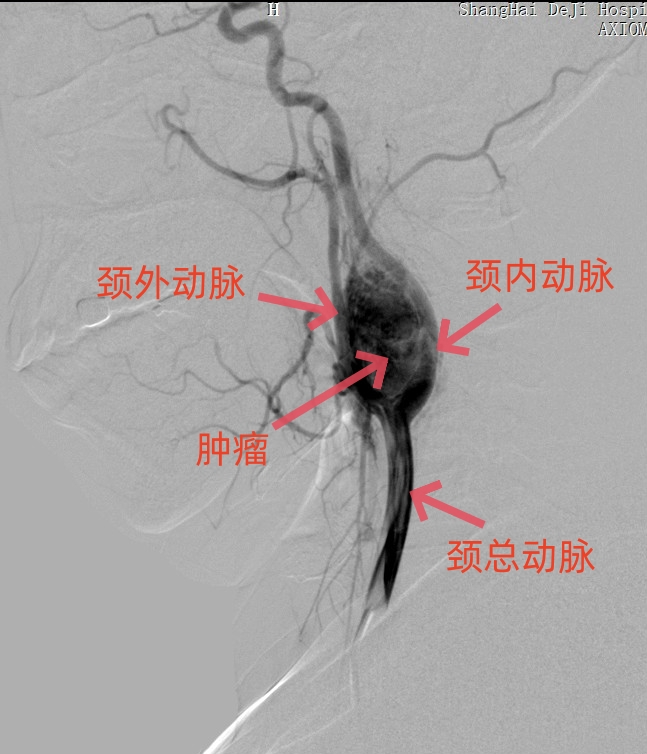

影像学是诊断颈动脉体瘤的重要工具之一。常用的影像学检查包括超声、CT扫描和磁共振成像(MRI)。超声可以提供血流动力学信息,帮助确定瘤体的位置和大小。CT扫描和MRI则可以提供更详细的解剖结构信息,帮助医生评估瘤体的形态和与周围组织的关系。